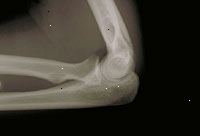

X-ray lokte

X-ray může být prováděna ambulantně nebo v rámci Vašeho pobytu v nemocnici. Postupy se mohou lišit v závislosti na nemoci a praxí svého lékaře.